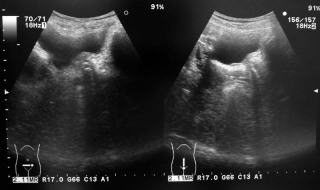

エコー

よく観察すると尿道にシャドウを引く高輝度のものが映ります。尿道の高輝度像は偽陽性も多いためこれだけで自信をもって女性尿道結石と言い切るのは多少不安があります。